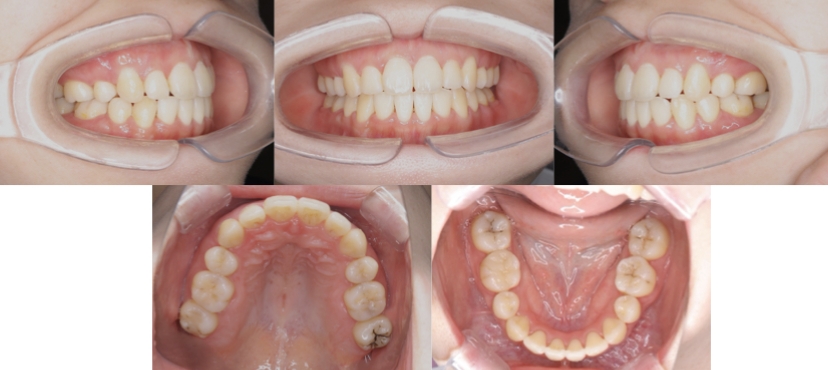

BEFORE

AFTER

症例3

叢生

抜歯

ブラケット矯正

上下顎叢生(上下の前歯のガタガタ)のケースです。

装置はラビアル(上下表側)で、上下顎の小臼歯を4本抜歯を行っています。抜歯したスペースを使って、上下の前歯の後方移動と叢生(ガタガタ)の改善を行っています。

主訴 八重歯を治したい。

年齢・性別 25歳 女性

お住まいの地域 神奈川県川崎市

治療方針 抜歯スペースを利用して上前歯の叢生(ガタガタ)の改善

抜歯部位 上下顎左右第一小臼歯

使用装置 ラビアル(上下表側)、顎間ゴム

治療期間 1年11か月

治療回数 16回

リテーナー クリアリテーナー